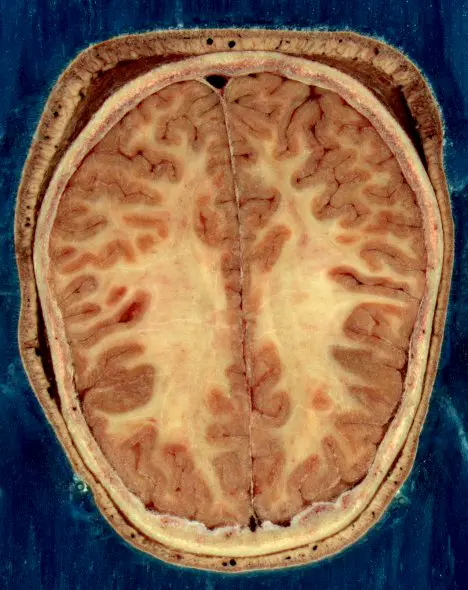

Le binge drinking a de graves répercussions anatomiques chez les hommes. Leurs cerveaux présentent des perturbations au niveau de la connectivité neuronale dans la matière blanche. La matière blanche est composée de faisceaux de fibres qui connectent les différentes régions de matière grise et transmettent les communications entre les cellules nerveuses. Lorsque la matière blanche est atteinte, le câblage par lequel passe l'influx nerveux est moins performant.

Or à l'adolescence, il y a une diminution de la masse de matière grise afin d'éliminer les connexions neuronales inutiles tandis que la matière blanche s'intensifie pour accélérer la vitesse de connexion sur la myéline.

Contrairement aux garçons, les filles ne perdent pas la densité de leur matière blanche. Selon le Pr Mickael Naassila, ce résultat serait certainement dû au fait que "le cerveau des jeunes filles finit sa maturation plus tôt dans l'adolescence, alors qu'elle continue de progresser chez l'homme jeune adulte". Le professeur n'exclut pas que la matière blanche des femmes subisse des altérations "mais plus subtiles", explique-t-il. Néanmoins, elles voient leur matière grise altérée.

C'est la matière grise du cerveau qui contient les corps cellulaires de nos neurones. Les structures de la matière grise traitent l'information provenant des organes sensoriels ou d'autres régions du cerveau constituées de matière grise.

La matière grise du cerveau contient les corps cellulaires des cellules nerveuses (neurones) alors que la matière blanche contient les fibres nerveuses (axones des cellules nerveuses) entourées d'une gaine de myéline protectrice.

La myéline, qui donne la couleur blanche, agit comme un isolant qui facilite la transmission des signaux transmis par les fibres nerveuses.

La matière grise est distribuée dans le cortex cérébral et plus profondément dans les noyaux des cellules nerveuses, dans le tronc cérébral et la colonne vertébrale.